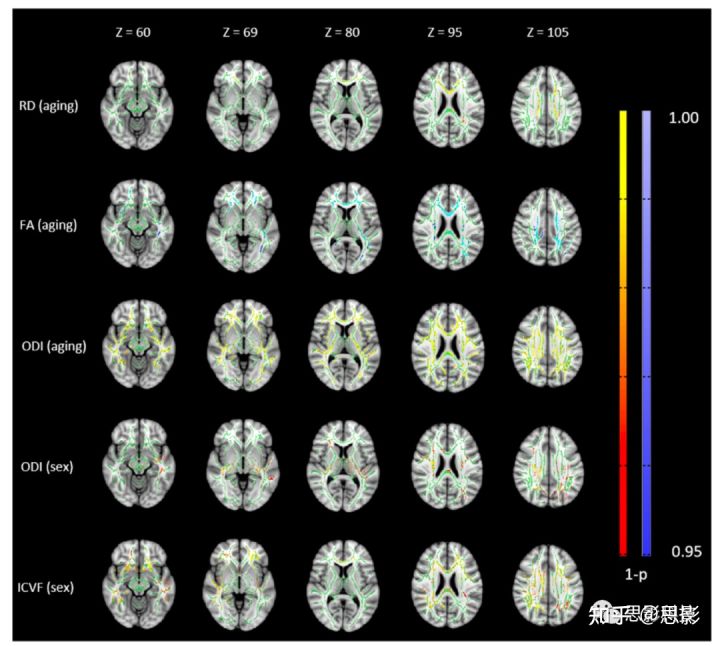

图7的前三行显示了RD、FA和ODI中年龄效应的校正p值图像的子集。RD和ODI随年龄增长而增加,FA则随年龄增长而减少。使用TBSS分析,AD、MD、P0和ICVF在这个青壮年人群中没有显示出年龄依赖性。图7最底下两行显示了ODI和ICVF中性别差异的空间分布。DTI和P0未检测到性别差异。此外,男性的ODI和ICVF高于女性。完整数据可在 http://dx.doi.org/10.7910/DVN/KUYSDI下载。

图7 TBSS分析全脑白质骨架的扩散指标,以显示年龄效应和性别差异的空间分布。

校正后的p值(如(1-p))叠加在标准T1W图像上。绿色体素表示白质骨骼。

红-黄编码为正相关,蓝-浅蓝色编码为负相关。颜色等级是0.95至1。

TBSS和ROI

ROI分析的结果与TBSS结果一致,即ODI在大多数白质骨骼中随着年龄的增长显著增加(图7),而MD,P0,ICVF对衰老不敏感。TBSS分析也显示,随着FA的降低,RD和ODI增加的趋势。DTI和P0在使用TBSS时没有发现任何性别差异,这与ROI研究是一致的。与表2的ROI结果相似,TBSS分析显示男性的ODI和ICVF高于女性